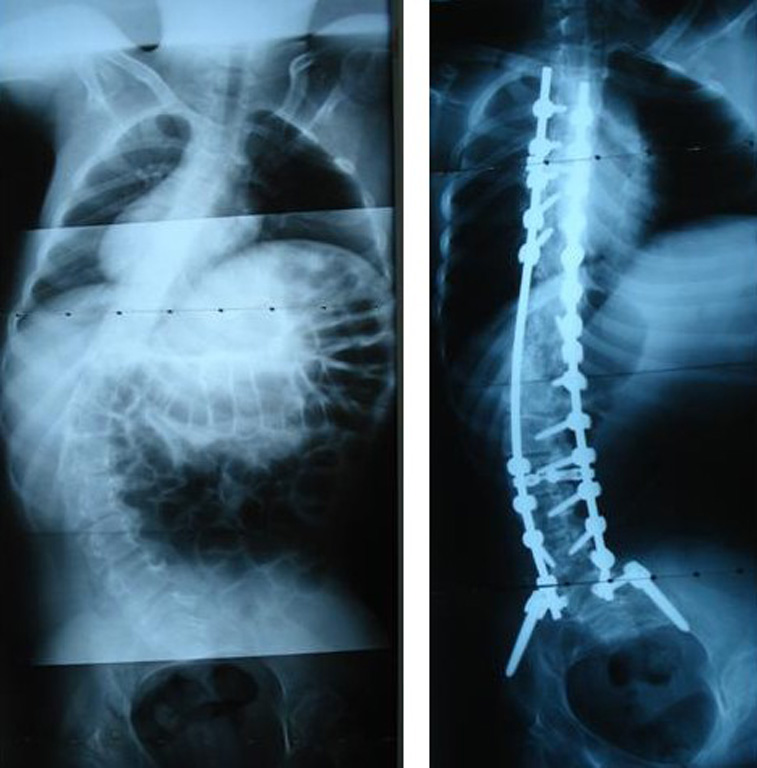

Grafilerle Skolyoz